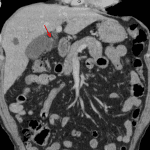

- Gallbladder is distended with diffuse wall thickening and a 5 mm stone in the cystic duct

- Tiny hypoattenuating structure adjacent to the gallbladder in hepatic segment 5

- 1.5 cm fluid density structure in segment 5 of the liver likely represents a cyst. Multiple additional subcentimeter hypodensities are too small to characterize

- Acute cholecystitis

Acute calculous cholecystitis. No biliary duct dilation. Recommend surgical consultation.

A tiny hypoattenuating structure adjacent to the gallbladder in hepatic segment 5 may represent early hepatic abscess formation.